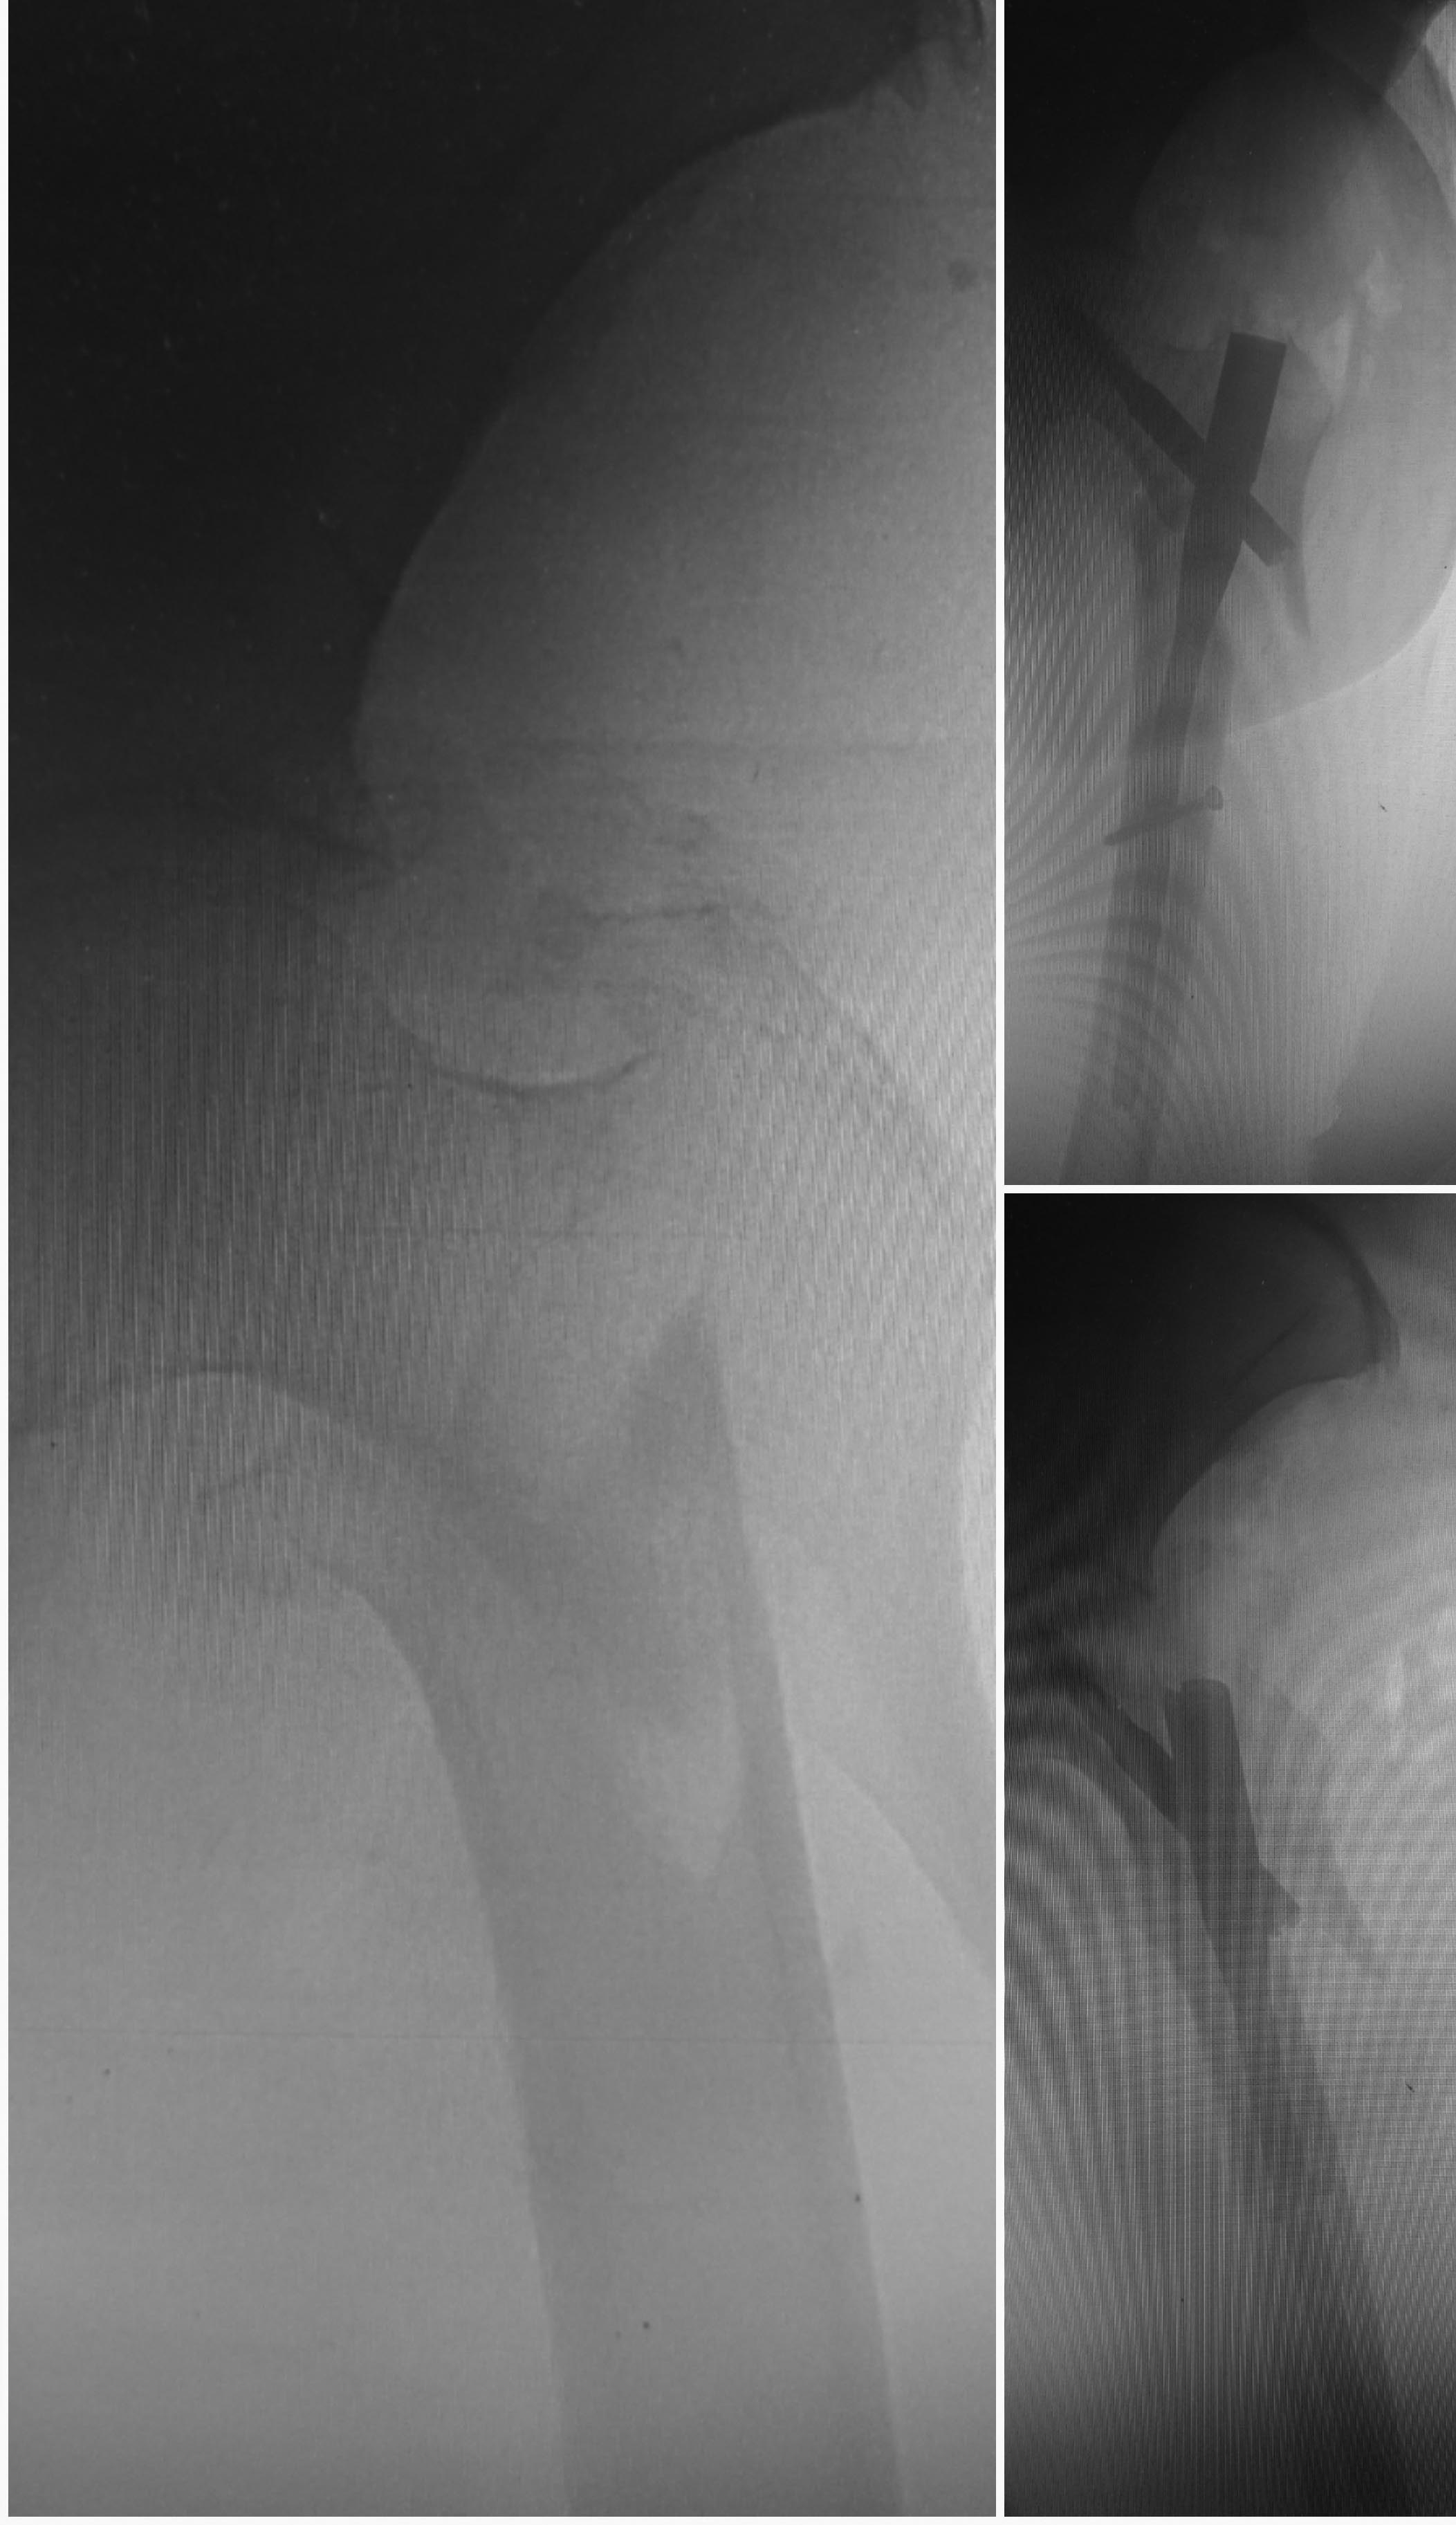

Больная, 90 лет. Остеосинтез Y-PFN. Переделывать не планируется.

Репозиция до введения гвоздя не была достигнута. На будущее, что нужно

при таком переломе делать, чтобы достичь репозиции. Спасибо.